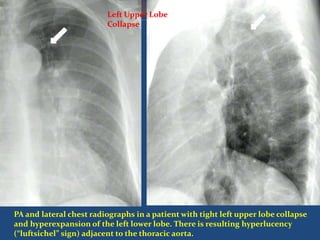

PA and lateral chest radiographs in a patient with tight left upper lobe collapse

and hyperexpansion of the left lower lobe. There is resulting hyperlucency

(“luftsichel” sign) adjacent to the thoracic aorta.

Left Upper LobeCollapse  Left lower lobe has increased in volume to compensate volume loss and can be seen wrapping round the medial side of the collapsed upper lobe. This is known as the 'Luftsichel' (air crescent) sign .

PA and lateralchest radiographs in a patient with tight left upper lobe collapse and hyperexpansion of the left lower lobe. There is resulting hyperlucency (“luftsichel” sign) adjacent to the thoracic aorta. Left Upper Lobe Collapse